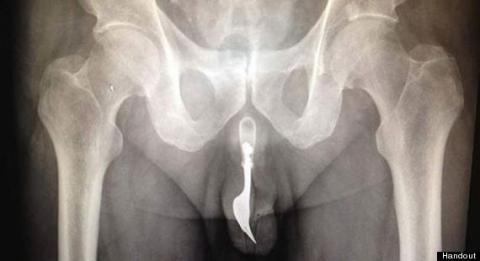

Nĩa trong dương vật

Hồi tháng 8, khoa cấp cứu Bệnh viện Canberra, Australia tiếp nhận một bệnh nhân 70 tuổi bị đau và chảy máu ở bộ phận sinh dục. Bệnh nhân thừa nhận mình cố tình nhét chiếc nĩa vào vùng kín để thỏa mãn ham muốn dục vọng. Thật không may, chiếc nĩa bị mắc kẹt bên trong. Mặc dù vậy ông cũng phải mất 12 giờ đồng hồ chịu đựng đau đớn và bất đắc dĩ phải đến bệnh viện nhờ giúp đỡ. Do nĩa chui vào sâu bên trong nên các bác sĩ không tìm thấy nguyên nhân gây ra sự khó chịu. Tuy nhiên, cuối cùng chiếc nĩa cũng được kéo ra bằng kìm kẹp và chất bôi trơn. Người đàn ông này đã được xuất viện mà không bị chấn thương lâu dài.